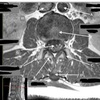

19

Q

What is letter A?

A

SPINAL CORD

20

What is letter B?

LIGAMENTUM FLAVUM

21

What is letter C?

SPINOUS PROCESS

22

What is letter D?

CSF

23

What is letter E?

VERTEBRAL BODY

24

What is letter F?

STERNUM

25

What is letter H?

SUPRASTERNAL NOTCH